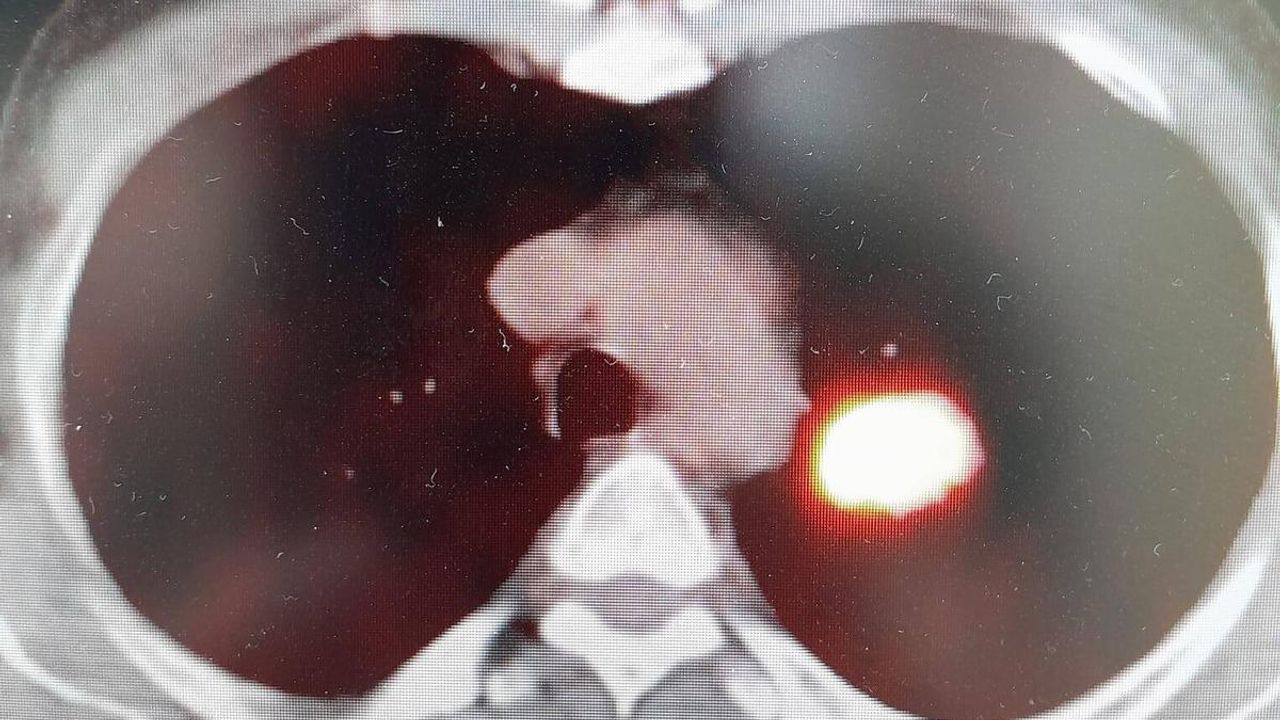

Toplumu en çok etkileyen, hastaların ve yakınlarının kabusu olan kanser hastalığı gerçeğine değinen uzmanlar, bilim ve teknolojide yaşanan gelişmelere rağmen, hala kanser tedavisinde erken tanı koymanın yerini alabilecek bir tedavi yöntemi bulunamadığında hemfikir.  Altınbaş Üniversitesi Tıp Fakültesi Göğüs Hastalıkları Bölüm Başkanı Prof. Dr. Şevket Özkaya, “Bugün bilinen en önemli husus, yaşayan her hücrenin sonunun kanser ve ölüm olacağı. Örneğin, bir insanın akciğer kanserine veya meme kanserine yakalanma yaşı genetik olarak kodlanmıştır. Tıp dünyası eğer bir insan, başka hastalıklardan hayatını kaybetmeyip, 150 veya 170 yaşına kadar yaşarsa mutlaka kanser hastası olacağını öngörüyor. Eğer sigara kullanıyor veya kanserojen maddelere maruz kalıyorsanız, bu kansere yakalanma yaşınızı düşüren bir faktör. Örneğin; 150 veya 170 yaşında akciğer kanseri olacak bir kişi, sigara içtiği için bu yaş 100’e düşüyor. Eğer ailede kanser öyküsü varsa bu yaş daha da düşüyor. Ve 45 yaşından sonra her an kanser gelişmesi ile karşı karşıya kalınıyor” dedi.

Kanser söz konusu olduğunda hastalara “hastalıktan korkma, geç kalmaktan kork” dediklerini belirten Özkaya, “Çünkü kanser, erken evrede yakalanırsa tamamen kurtulabileceğiniz bir hastalıktır. Sağlık Bakanlığımızın kanser taramaları için kurduğu Kanser Erken Teşhis Tarama ve Eğitim Merkezleri ‘KETEM’ birimleri yıllardır bu konuda çok başarılı işlere imza atıyorlar. Topluma en faydalı sağlık hizmetlerinden biri olarak halkımıza kadın ve erkek kanserleri için erken tanı ve tedavi hizmetlerini ücretsiz olarak vermeye devam ediyorlar” diyerek erken tanının önemini vurguladı.